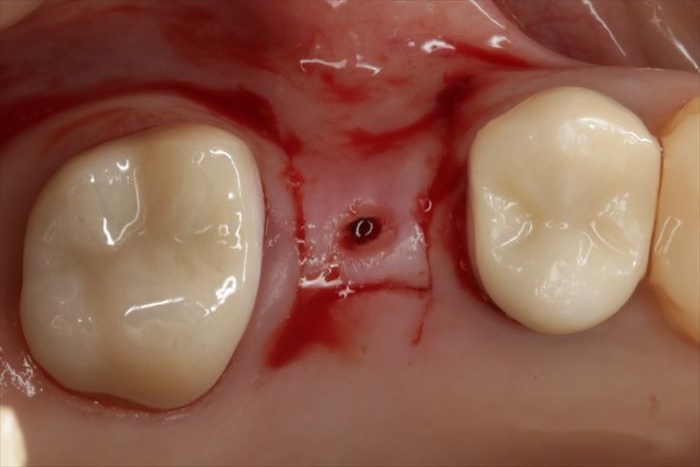

いよいよ本日インプラント埋入オペを行います。

まずはサージカルステントの適合を確認します。

修正が可能な深さまでドリリングして、深度ゲージを挿入してデンタルレントゲン写真を撮影します。

デンタルレントゲン写真において想定通りの角度であることから、ドリリングのステップを進めます。